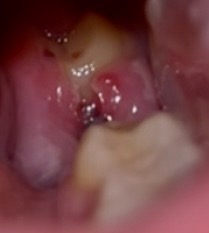

Poslednou dobou tu vidím veľmi veľa diskusii o trhani zubov 😂 chcem sa opýtať, v piatok mi trhali osmičku zub (hore červená čiarka je po diere- už sa to pekne zrastoo skoro) ale chcem sa spytat či je normslne to ďasno pod tým, sfarbilo sa mi do takej šedej. A keď máte niekto skúsenosti. Za koľko dni sa to zahojilo? Alebo mám navštíviť zubára ? Toto je vlstne jedine čo má boli už len.

Mňa bolelo intenzívne tri týždne ale museli mi ho vysekavat. Sive som nemala nič, ale asi tri dni akoby biely povlak. Som sa bála že to hnisa ale to bola súčasť hojenia. Keby to sive nezmizne za pár dní tak by som minimálne volala zubarke

Ahoj, ja mám vytrhnuté tri osmičky, dve sa hojili uplne bez problemov, ziadne extra bolesti a tá posledná ma po vytrhnutí bolela strašneee, mala som pocit, že ma celá sánka bolí, bez Flectoru som nevedela ani fungovat vyse tyzdna a mala som to tam presne aj takto sive ako ty. Tuším dake dva tyzdne kým mi tie bolesti prešli a zahojilo sa to potom v pohode. Ja keby som bola v tom čase doma tak navštívim zubára, len som akurát bola pracovne v zahraničí, čiže som to musela zvládnuť len s liekmi proti bolesti a na kontrolu som isla po 10 dnoch od trhania a aj ked ma to ešte pobolievalo, zubár povedal, že sa to hojí ok a mám si to len vyplachovať.

Áno, to sa hojí vždy to je také sivé.Vyplachuj si to niečim